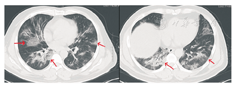

患者男,47岁,黑龙江省哈尔滨市人。因"发热5 d"于2020年1月21日收入我院发热留观病房。既往健康,否认慢性病史及传染病史。患者为火车司机,往返于哈尔滨——武汉区间。发病前两周曾两次随车到达武汉,并在武汉火车站站台逗留。2020年1月16日开始出现发热,体温在37.5~39 ℃,伴畏寒,无寒战。无咳嗽及咯痰,无喘息及呼吸困难。入院前1 d曾有轻微腹泻症状,排稀便两次,未见脓血。入院后查体:一般状态尚可,呼吸平稳,体温38.2 ℃,脉搏108次/min,呼吸16次/min,血压140/95 mmHg(1 mmHg=0.133 kPa)。球结膜轻度充血,双肺听诊呼吸音清,未闻及干湿啰音。入院当日在我院发热门诊行血常规检查:白细胞(WBC)6.14×109/L,中性粒细胞占比0.560,淋巴细胞占比0.337,淋巴细胞绝对计数2.07×109/L,单核细胞占比0.103,红细胞及血小板计数正常。胸部CT:左肺及右肺上下叶可见斑片影,边界模糊。影像学诊断:左肺及右肺上下叶炎性改变(图1)。入院当日市疾控中心行咽拭子2019-nCoV核酸检测阴性,其他相关检查结果:C-反应蛋白16.8 mg/L(参考值0~8 mg/L),红细胞沉降率38.00 mm/1 h(参考值0~15 mm/1 h),降钙素原0.10 ng/mL(参考值0~0.046 ng/mL),肌红蛋白203 ng/mL(参考值0~154.9 ng/mL),肌酸激酶1 149.60 U/L(参考值38~174 U/L),G-脂多糖、肝肾功能、凝血功能正常。相关病原学检查:甲型流感病毒、乙型流感病毒、副流感病毒-2型、嗜肺军团菌、肺炎支原体、肺炎衣原体、Q热立克次体、腺病毒、呼吸道合胞病毒、风疹病毒、单纯疱疹病毒、巨细胞病毒、弓形虫IgM抗体均阴性。EBV DNA定量<5.0×102拷贝/mL。入院当日开始静脉点滴盐酸莫西沙星氯化钠注射液(0.4 g/d),口服磷酸奥司他韦胶囊(75 mg/次,2次/d),补液对症治疗。1月23日,患者仍有间断高热,体温可达40 ℃。偶有轻微干咳,无痰。市疾控中心第2次咽拭子2019-nCoV核酸检测仍为阴性,我院复查血常规:WBC 4.89×109/L,中性粒细胞占比0.583,淋巴细胞占比0.319,淋巴细胞绝对计数1.56×109/L,单核细胞占比0.098。胸部CT:双肺可见斑片影及磨玻璃影,边界模糊。影像学诊断:双肺炎性改变(图2)。咽拭子细菌培养、血细菌+真菌培养未检出病原体。继续给予上述药物治疗,同时行物理降温,未应用退热药物。因两次2019-nCoV核酸检测阴性,建议患者回家中自行隔离治疗。1月24日患者仍有发热,咳嗽频繁,咯白痰,且患者配偶亦出现发热症状,即到我院急诊内科留观隔离,继续予盐酸莫西沙星氯化钠注射液静脉点滴、口服磷酸奥司他韦胶囊(两种药物剂量同上)。1月26日患者仍发热,体温最高达38.5 ℃,自觉胸闷、呼吸急促,查动脉血气分析:PaO2/FiO2:342 mmHg。血常规:WBC 4.37×109/L,中性粒细胞占比0.687,淋巴细胞占比0.197,淋巴细胞绝对计数0.86×109/L,单核细胞占比0.115。胸部CT:双肺可见淡片影,磨玻璃影,范围较前扩大,边界不清。影像学诊断:双肺炎症(图3)。1月27日我院组织院内专家会诊,认为该患者虽然两次2019-nCoV核酸检测阴性,但结合流行病学史及临床表现(高热,淋巴细胞计数进行性减少、肺部间质性病变且进行性加重),不能排除2019-nCoV感染,申请市疾控中心行第3次咽拭子2019-nCoV核酸检测,结果仍为阴性。患者仍维持原治疗方案治疗。1月28日患者体温趋于正常,自行离院,在家中继续隔离治疗。每3日对患者进行电话随访,患者未再出现发热,咳嗽、咯痰明显缓解,未出现呼吸困难。因疫情期间特殊情况,未到我院进行相关复查。